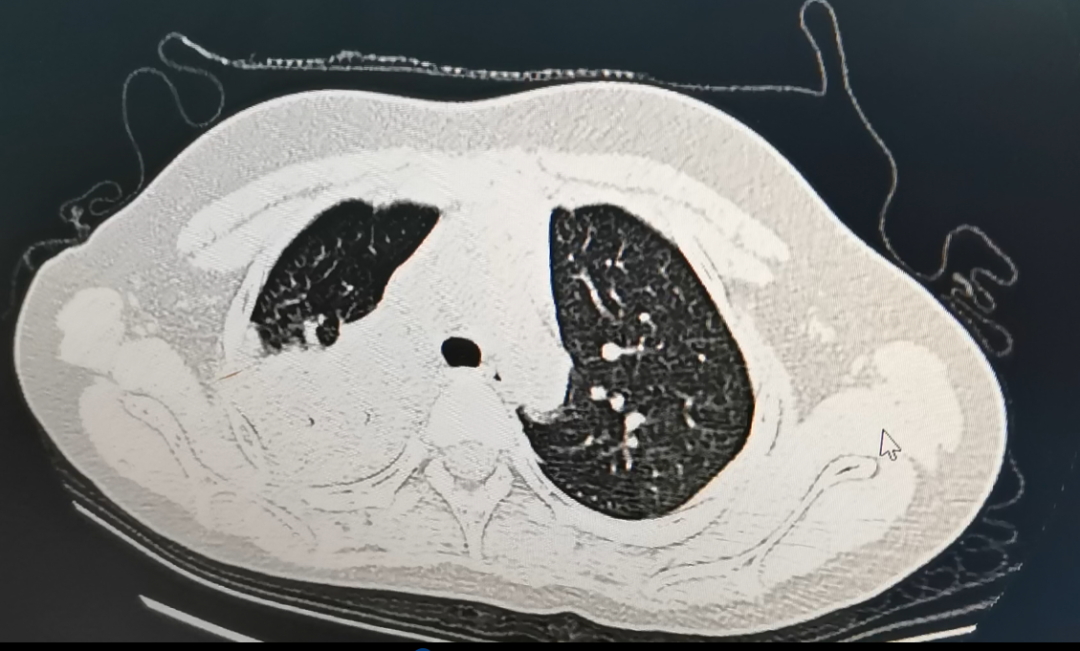

经过CT检查发现

她感染了肺炎支原体

肺部变成了“白”肺

经过医生检查,孩子整个右肺大部分已经变成了白肺状,肺部存在病灶,经过检测确诊为支原体肺炎的感染。